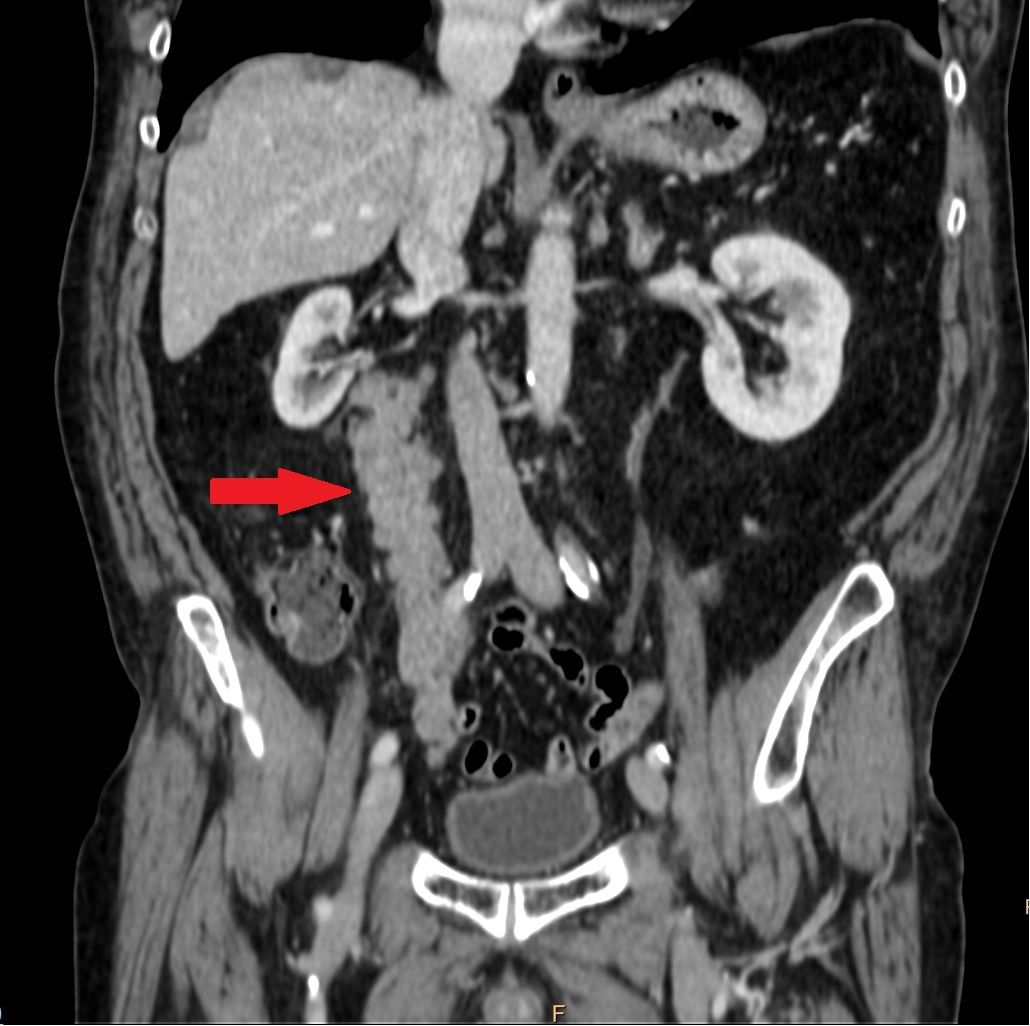

A former smoker 69-aged man graphic arts worker, with a past medical history of hypertension, hemicolectomy due to colon cancer 30 years ago (we ignore the disease state because no informs were provided), was diagnosed in 2004 of intermediate localized adenocarcinoma prostate cancer, Gleason 8 (4+4) (T3N0M0). He received 6 months of neoadjuvant hormonotherapy (LH-RH analogues) and radical radiotherapy (76Gy) including prostate and seminal vesicles. PSA nadir was 0.27ng/ml, and patient continued hormonal therapy as adjuvant treatment for 2 years. In June 2016, patient presented with hematuria and CT scan showed a retroperitoneal mass infiltrating all along the right ureter with secondary grade 2 hydronephrosis (Figure 1). Routine laboratory analysis was normal. Bone scan had no pathological alteration.

Figure 1 CT scan showed a retroperitoneal mass infiltrating all along the right ureter with secondary grade 2 hydronephrosis.

Our patient had a retroperitoneal mass infiltrating the right ureter with secondary grade 2 hydronephrosis. No other lymph nodes or metastases were observed. Biopsy of the mass revealed infiltration from prostate adenocarcinoma. Ureteral metastases from a prostate adenocarcinoma are extremely rare.9 The most common malignant tumors metastasizing to the ureter are breast followed by stomach and colorectal cancer. The incidence of prostatic originated metastasis is very low, with only 43 cases reported in the last century.9 Implantation could be produced by instrumentation, arterial embolism, and retrograde venous or lymphatic dissemination. The last one is the most accepted theory, but it would not match in this case because lymph node involvement was not present.10 Unlike most reported cases, our patient did not present any other metastatic disease. In parallel PSA value raised to 120ng/ml, with 35 ng/dl of testosterone, and hematuria stopped spontaneously.